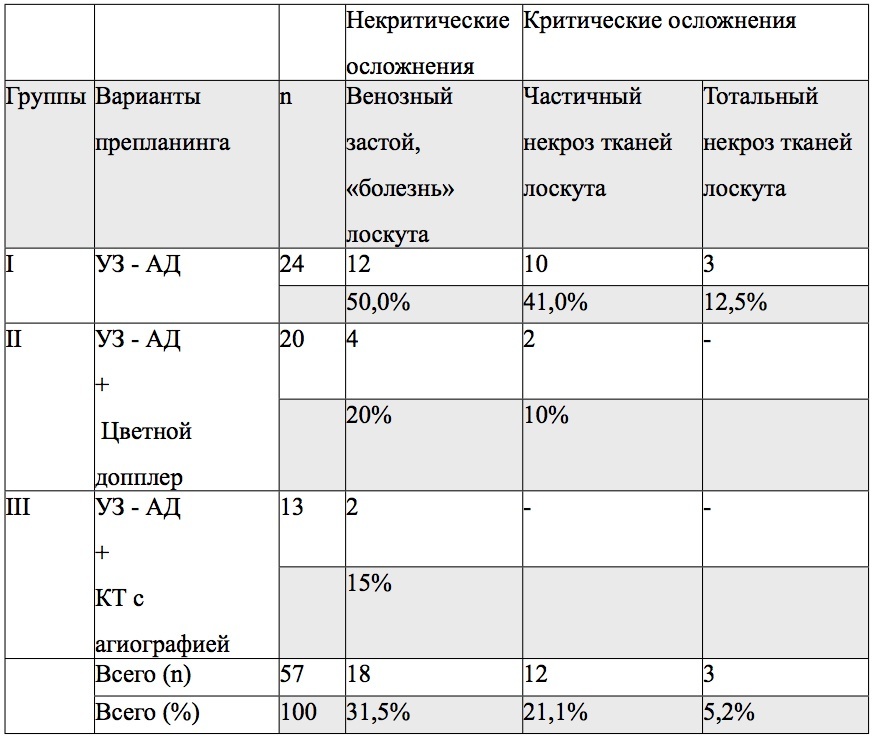

РЕЗУЛЬТАТЫ. Во всех случаях препланинга перфорантных лоскутов применение аудио-допплера позволило точно лоцировать зону выхода перфоранта в покровные ткани. Данное исследование являлось достаточным для определения дизайна лоскута, однако интраоперационно для визуализации и оценки самого перфоранта в питающей ножке дополнительно требовалось проводить его скелетирование и определять топографическое взаимоотношение с анатомическими ориентирами. При этом возможная анатомическая вариабельность направления оси и ветвления перфоранта в покровных тканях перманентно создают дополнительные технические трудности для хирургической бригады. Проводимые в этих случаях дополнительные манипуляции с тканями и сосудами, соответствующее увеличение объема дессекции тканей и времени операции негативно отражаются на результатах пластики. Так, в I группе операций венозный застой и «болезнь» лоскута встречались в 12 случаях или у половины пациентов (Таблица 1). Довольно значимым был и процент частичных некрозов тканей, чаще в дистальных зонах лоскутов – 41% (10 случаев). Эти пациенты требовали проведения дополнительных ревизионных вмешательств или наложения вторичных швов. Полная утрата лоскутов зафиксирована в 12,5% (3 случая). Во II группе выполнение расширенного препланинга с применением цветной допплеровской визуализации на ультрзвуковом сканере Philips HD11 XE позволило до начала операции детерминировать размеры сосудов, выделять среди них доминирующий перфорант и направление его оси, что сократило время хирургического вмешательства, количество интраоперационных технических погрешностей и проблемных результатов пластики. В этой группе венозный застой и «болезнь» лоскута встречались в 20% (4 случая), частичный некроз тканей лоскута – 10% (2 случая), критических осложнений с тотальным некрозом тканей лоскута не было. В III группе, где был применен вариант препланига с использованием аудио-допплера в сочетании с КТ с ангиографией при помощи мультисрезового компьютерного томографа, хирургическая бригада еще до начала операции имела достаточную и исчерпывающую информацию в отношении искомых перфорантных сосудов. Визуализация размера, направления оси сосуда и его ветвей, точная проэкция на покровные ткани и их топографическое взаимоотношение со стабильными анатомическими ориентирами, позволили сократить объемы дессекции тканей и продолжительность операции. Соответственно в данной группе полностью отсутствовалии критические осложнения, а венозный застой, который отмечен в 2 случаях (15%) был купирован в течении 3-5суток медикаментозно.

Таблица 1.

Сравнительная характеристика результатов операций с использованием перфорантных лоскутов в группах пациентов с различными вариантами препланинга.

Примечания: n – количество операций с использованием перфорантных лоскутов; УЗ-АД – исследование перфоранта ультразвуковым аудио-допплером (Минидоп); КТ- исследование перфоранта на компьютерном томографе с ангиографией.